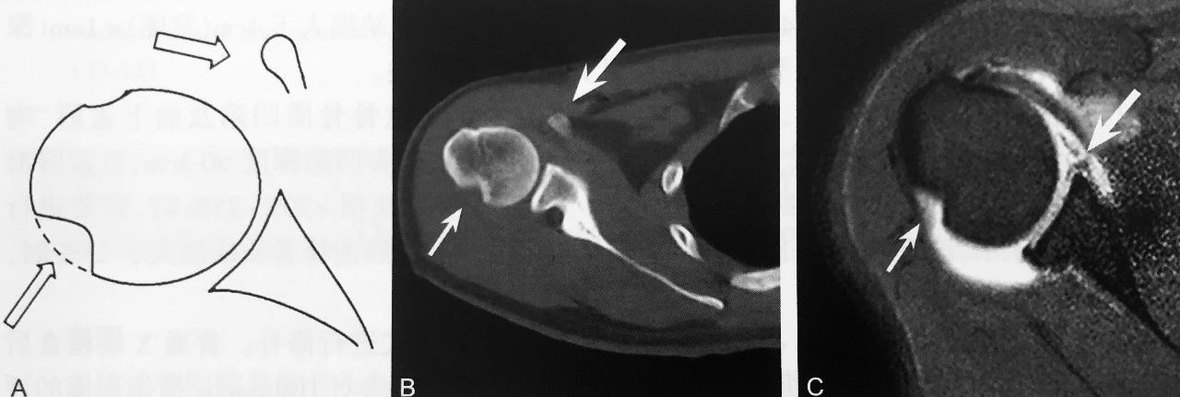

双 曲 奇 饼 征

A、B 图为同一患者,抑脂 T2WI 示上盂唇周围两条线样高信号,其中一条高信号代表上盂唇的撕裂,另外一条指的是盂唇上隐窝,形成双曲奇饼征,提示上盂唇由前向后撕裂,即 SLAP 损伤(箭头所示)

判读要点:

1、SLAP 损伤的特征性表现;

2、在肩关节常规 MRI 斜冠状位 T2WI 或 MRI 关节造影图像显示,上盂唇内出现两条高信号;

3、具有较高的特异性,但敏感性较低。